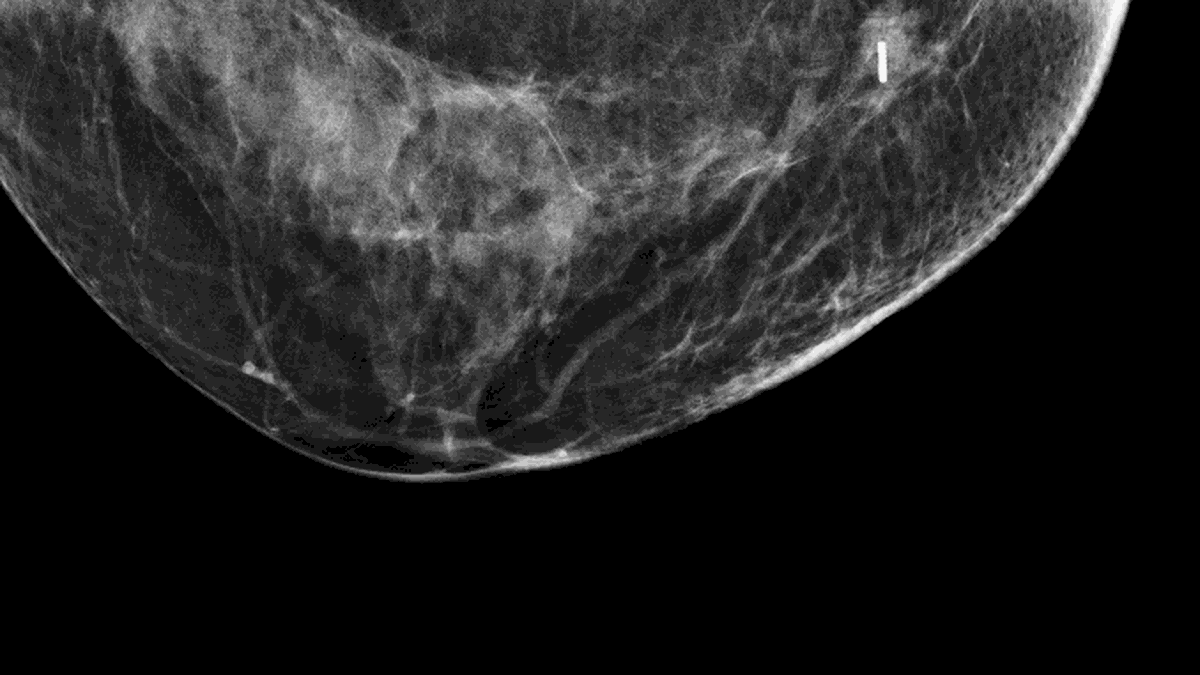

Le principe est de positionner un clip magnétique au sein de la tumeur, sous contrôle échographique, avant une chirurgie de cancer du sein par tumorectomie.

Le clip étant de taille millimétrique, sa mise en place est rapide et simple. Il est posé sous contrôle échographique en quelques minutes, après une anesthésie locale, en amont de la chirurgie.

Un clip millimétrique